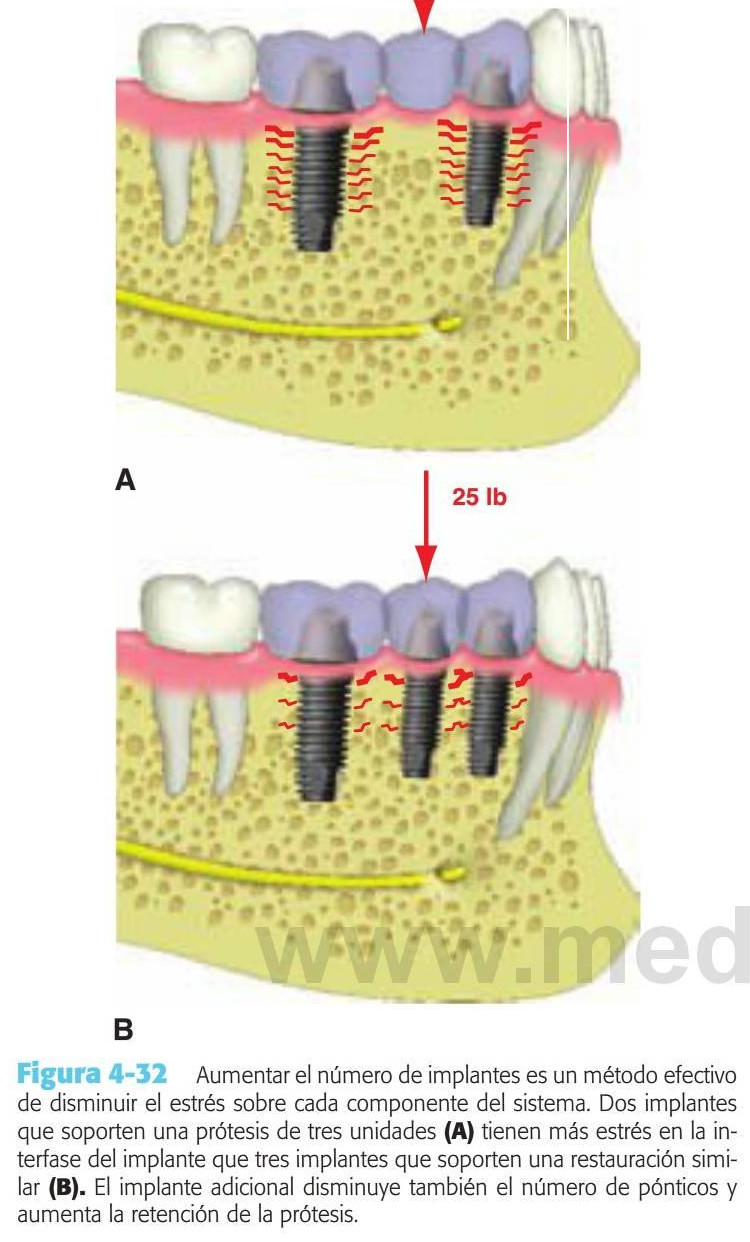

El estrés global sobre todo el sistema del implante puede reducirse aumentando el área sobre la que está aplicada la fuerza. El método más efectivo para aumentar el área de la superficie de soporte del implante consiste en aumentar el número de implantes de soporte de la prótesis (fig. 4-32). Por ejemplo, estudios previos de Bidez y Misch han demostrado que la fuerza distribuida sobre tres pilares da como resultado un estrés menos localizado en la cresta del hueso que con dos pilares. Este estudio se aplica únicamente a los implantes que están ferulizados conjuntamente. De ahí que, cuando las fuerzas están aumentadas, debería reducirse el número de pónticos y aumentar el de pilares de implantes, en comparación con la planificación de tratamiento para un paciente ideal con factores de fuerza mínimos.

La retención de la prótesis también se ve mejorada con un mayor número de pilares ferulizados. Este enfoque disminuye también la incidencia de las restauraciones no retenidas. Los implantes ferulizados disminuyen también las fracturas de la porcelana. Se reduce la cantidad global de estrés sobre el sistema, y los rebordes marginales de las coronas de los implantes son soportadas por las conexiones de las coronas ferulizadas, dando como resultado más fuerzas compresivas que las cargas intermitentes sobre la porcelana.